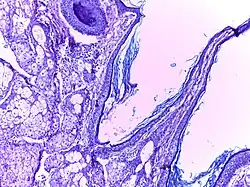

Benign cystic teratoma | Micrograph of Teratoma Ovary showing areas of cartilage, mucous glands, squamous epithelium and hair follicle. | Category: Histopathology of mature teratoma of ovary | teratoma |